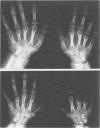

A brother and sister, children of normal parents are described. They had retinitis pigmentosa, causing near-blindness as a result of very narrow fields of vision, associated with metaphyseal chondrodysplasia and marked shortening of the metacarpals and terminal phalanges. Autosomal recessive inheritance is suggested with a common biochemical cause for all these defects. This apparently new association of retinitis pigmentosa with a systemic bone dysplasia emphasises that this not uncommon clinical diagnosis has a variety of different possible causes.